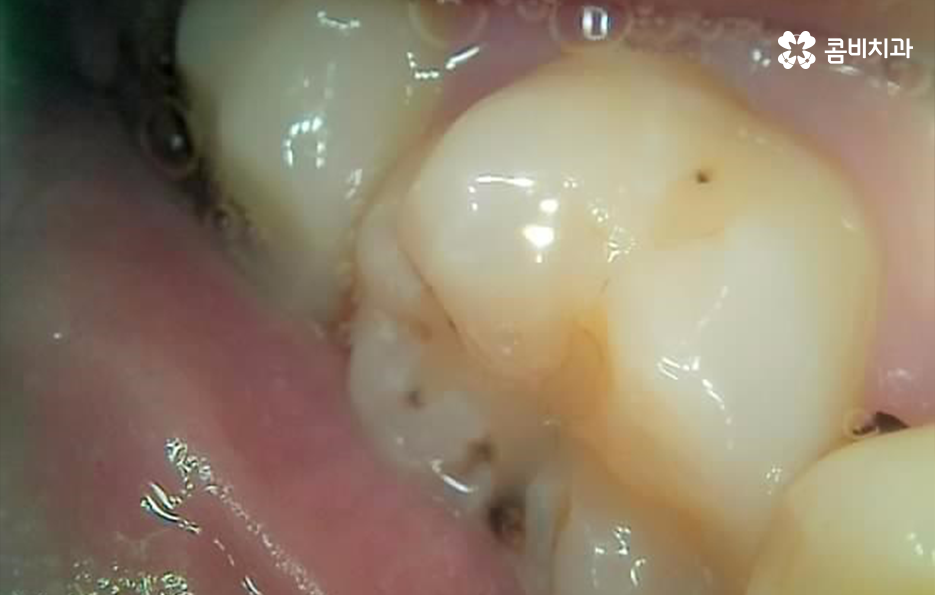

오늘은 어금니 치료에 많이 쓰이고 있는 어금니 레진 치료 후 관리에 대해 치료 케이스를 살펴보면서 자세히 알아볼 거예요

레진은 앞니 부터 어금니까지 치아 손상의 초기에 광범위하게 활용되고 있지만 특히 어금니 레진의 경우에는 교합면이나 특히 강하게 저작기능에서 압력을 받는 경우에 자주 깨지고 탈락 될 경우에는 인레이 치료를 하는 것이 적합할 수 있습니다

어금니 레진 치료 후에 레진 자체가 깨지거나 주변 치아가 깨진 경우에는 당장 안아파도 치과에서 재치료를 받는 것이 추가적인 파절을 예방하고 치아 내부로 충치가 발생되는 것을 예방할 수 있으며 특히 주변이 검게 변색되는 경우에는 착색인 경우도 있지만, 2차 충치가 이미 진행된 경우가 많기 때문에 통증과는 무관하게 치과 방문을 권하고 있어요